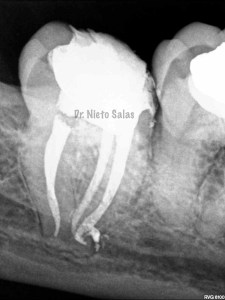

Y una en las demás proyecciones MESIO Y DISTO:

2. disculpe, en las imagenes de la entrada de los conductos, era dos conductos distales o era solo uno ?? muchas gracias y enhorabuena por el casa, es perfecto !!

3. Dr Nieto Salas, en la imagen en que se ven la camara con la entrada de los conductos y la gutapercha, el orificio de entrada en distal era muy ancho, a parte de conductos laterales, localizo un conducto o dos conductos ?? ( la duda es por lo ancho de la entrada). El caso es maravilloso. Le doy mi enhorabuena.

4. Hola Juan,

en ese caso en particular, el número de conductos era solamente uno, ya sabes que los conducto distales en muchas ocasiones tienen forma ovalada, con lo que la entrada puede corresponder con las imágenes.